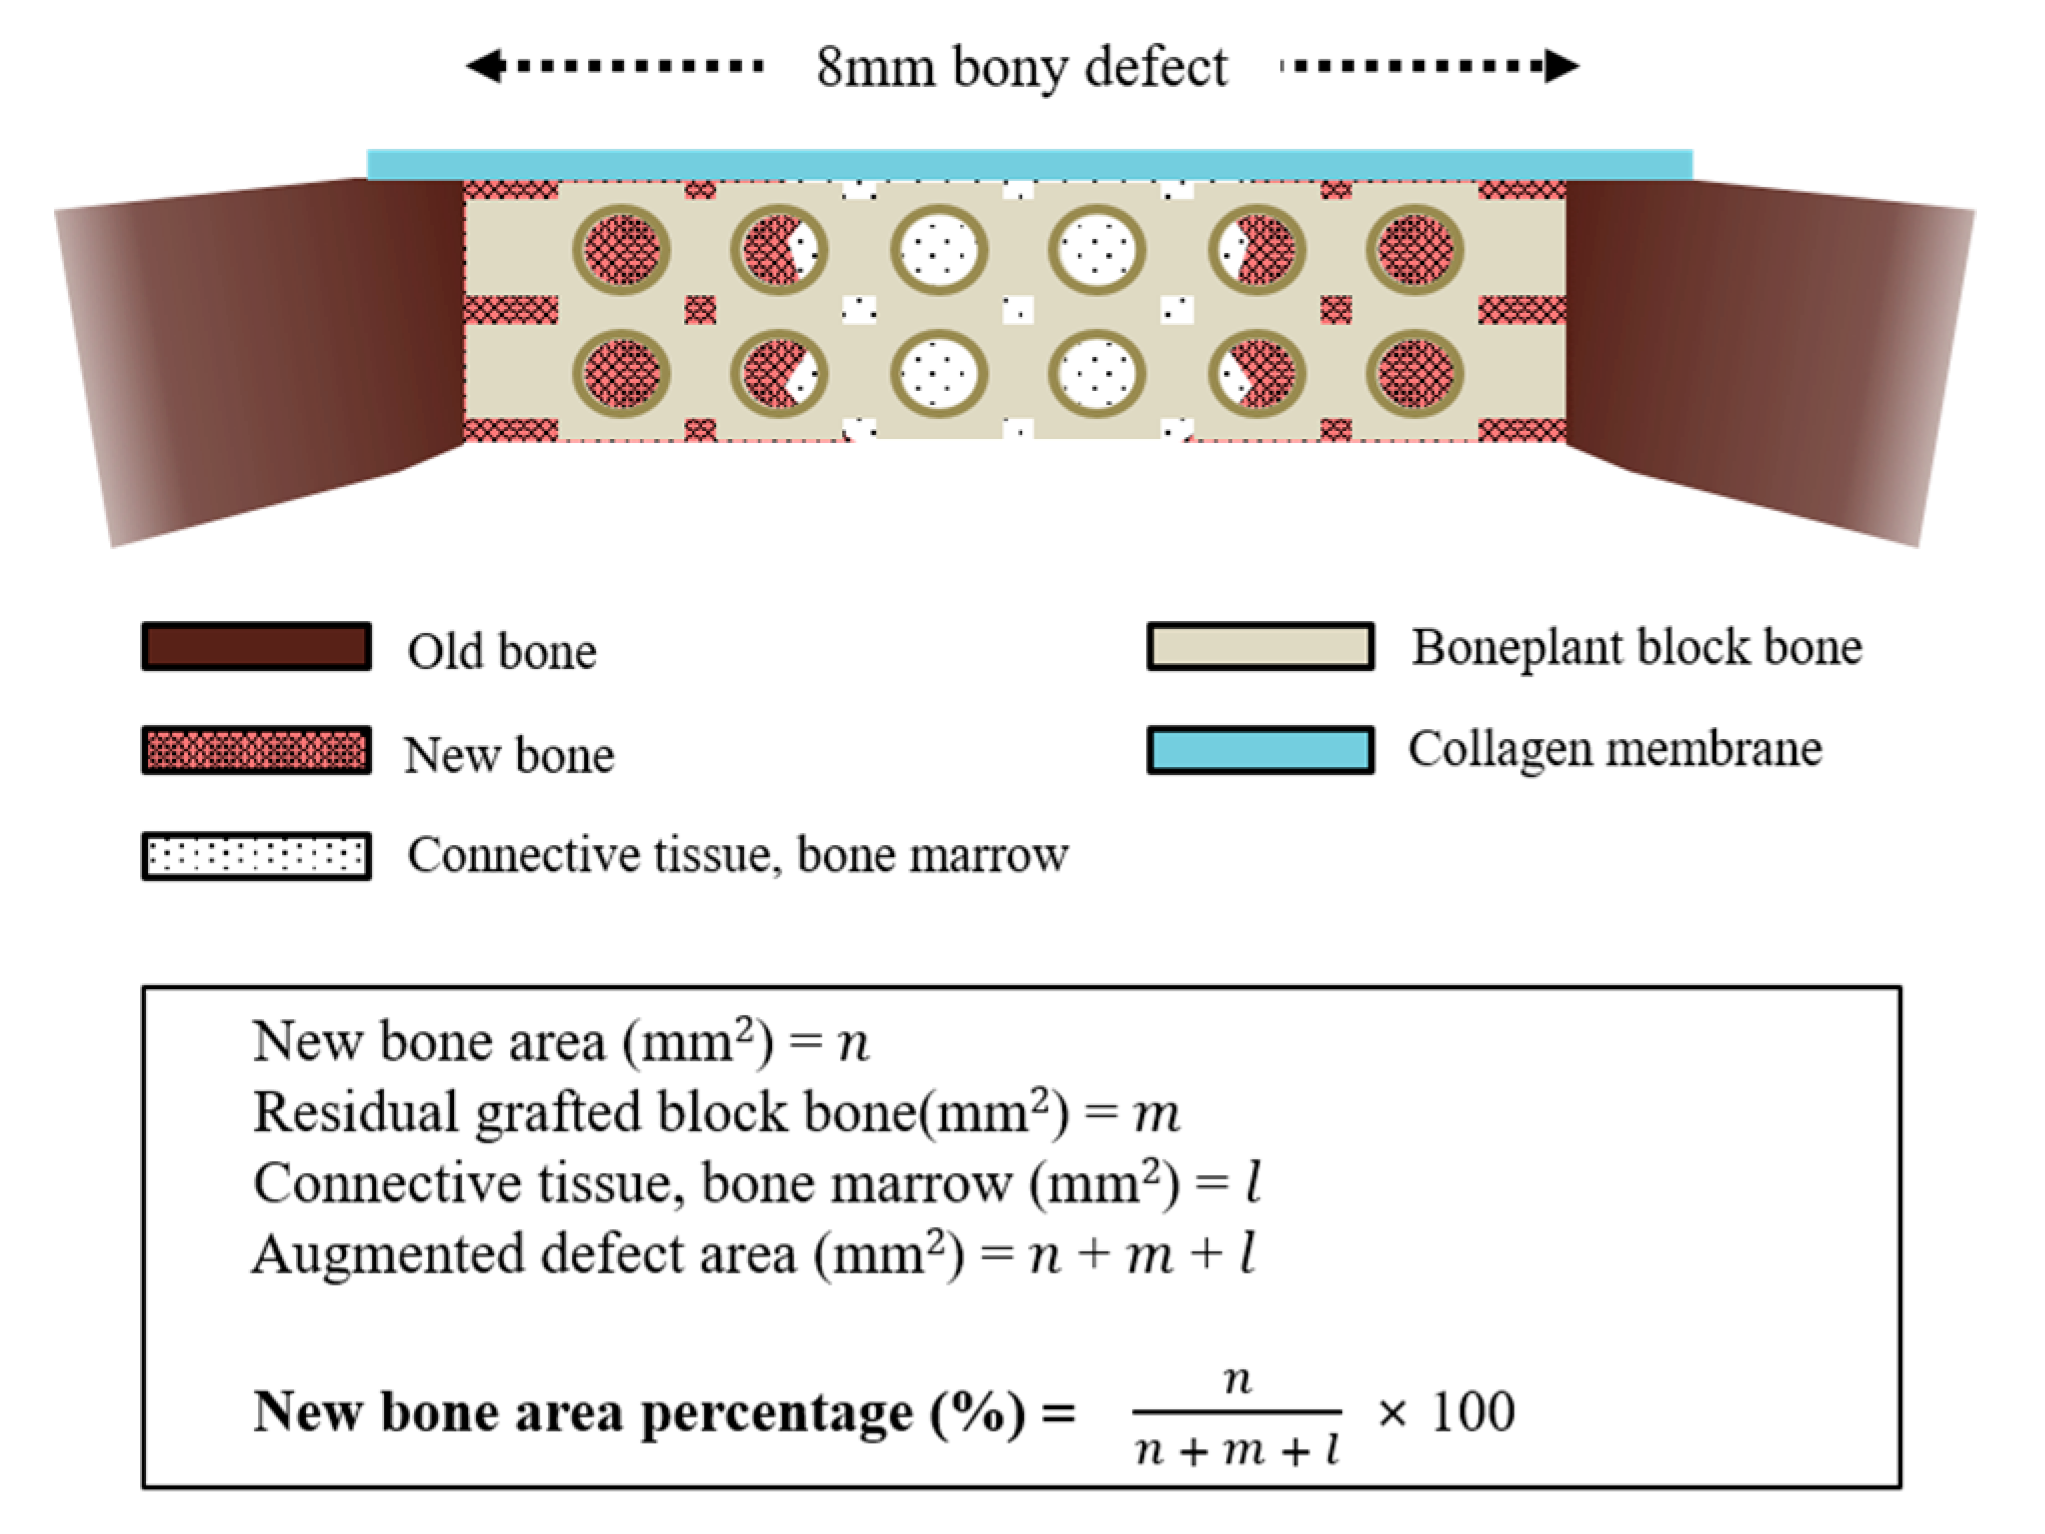

2.3.4. Histologic and Histometric Procedures

3.2.3. Histological Findings

3.2.4. Histometric Findings